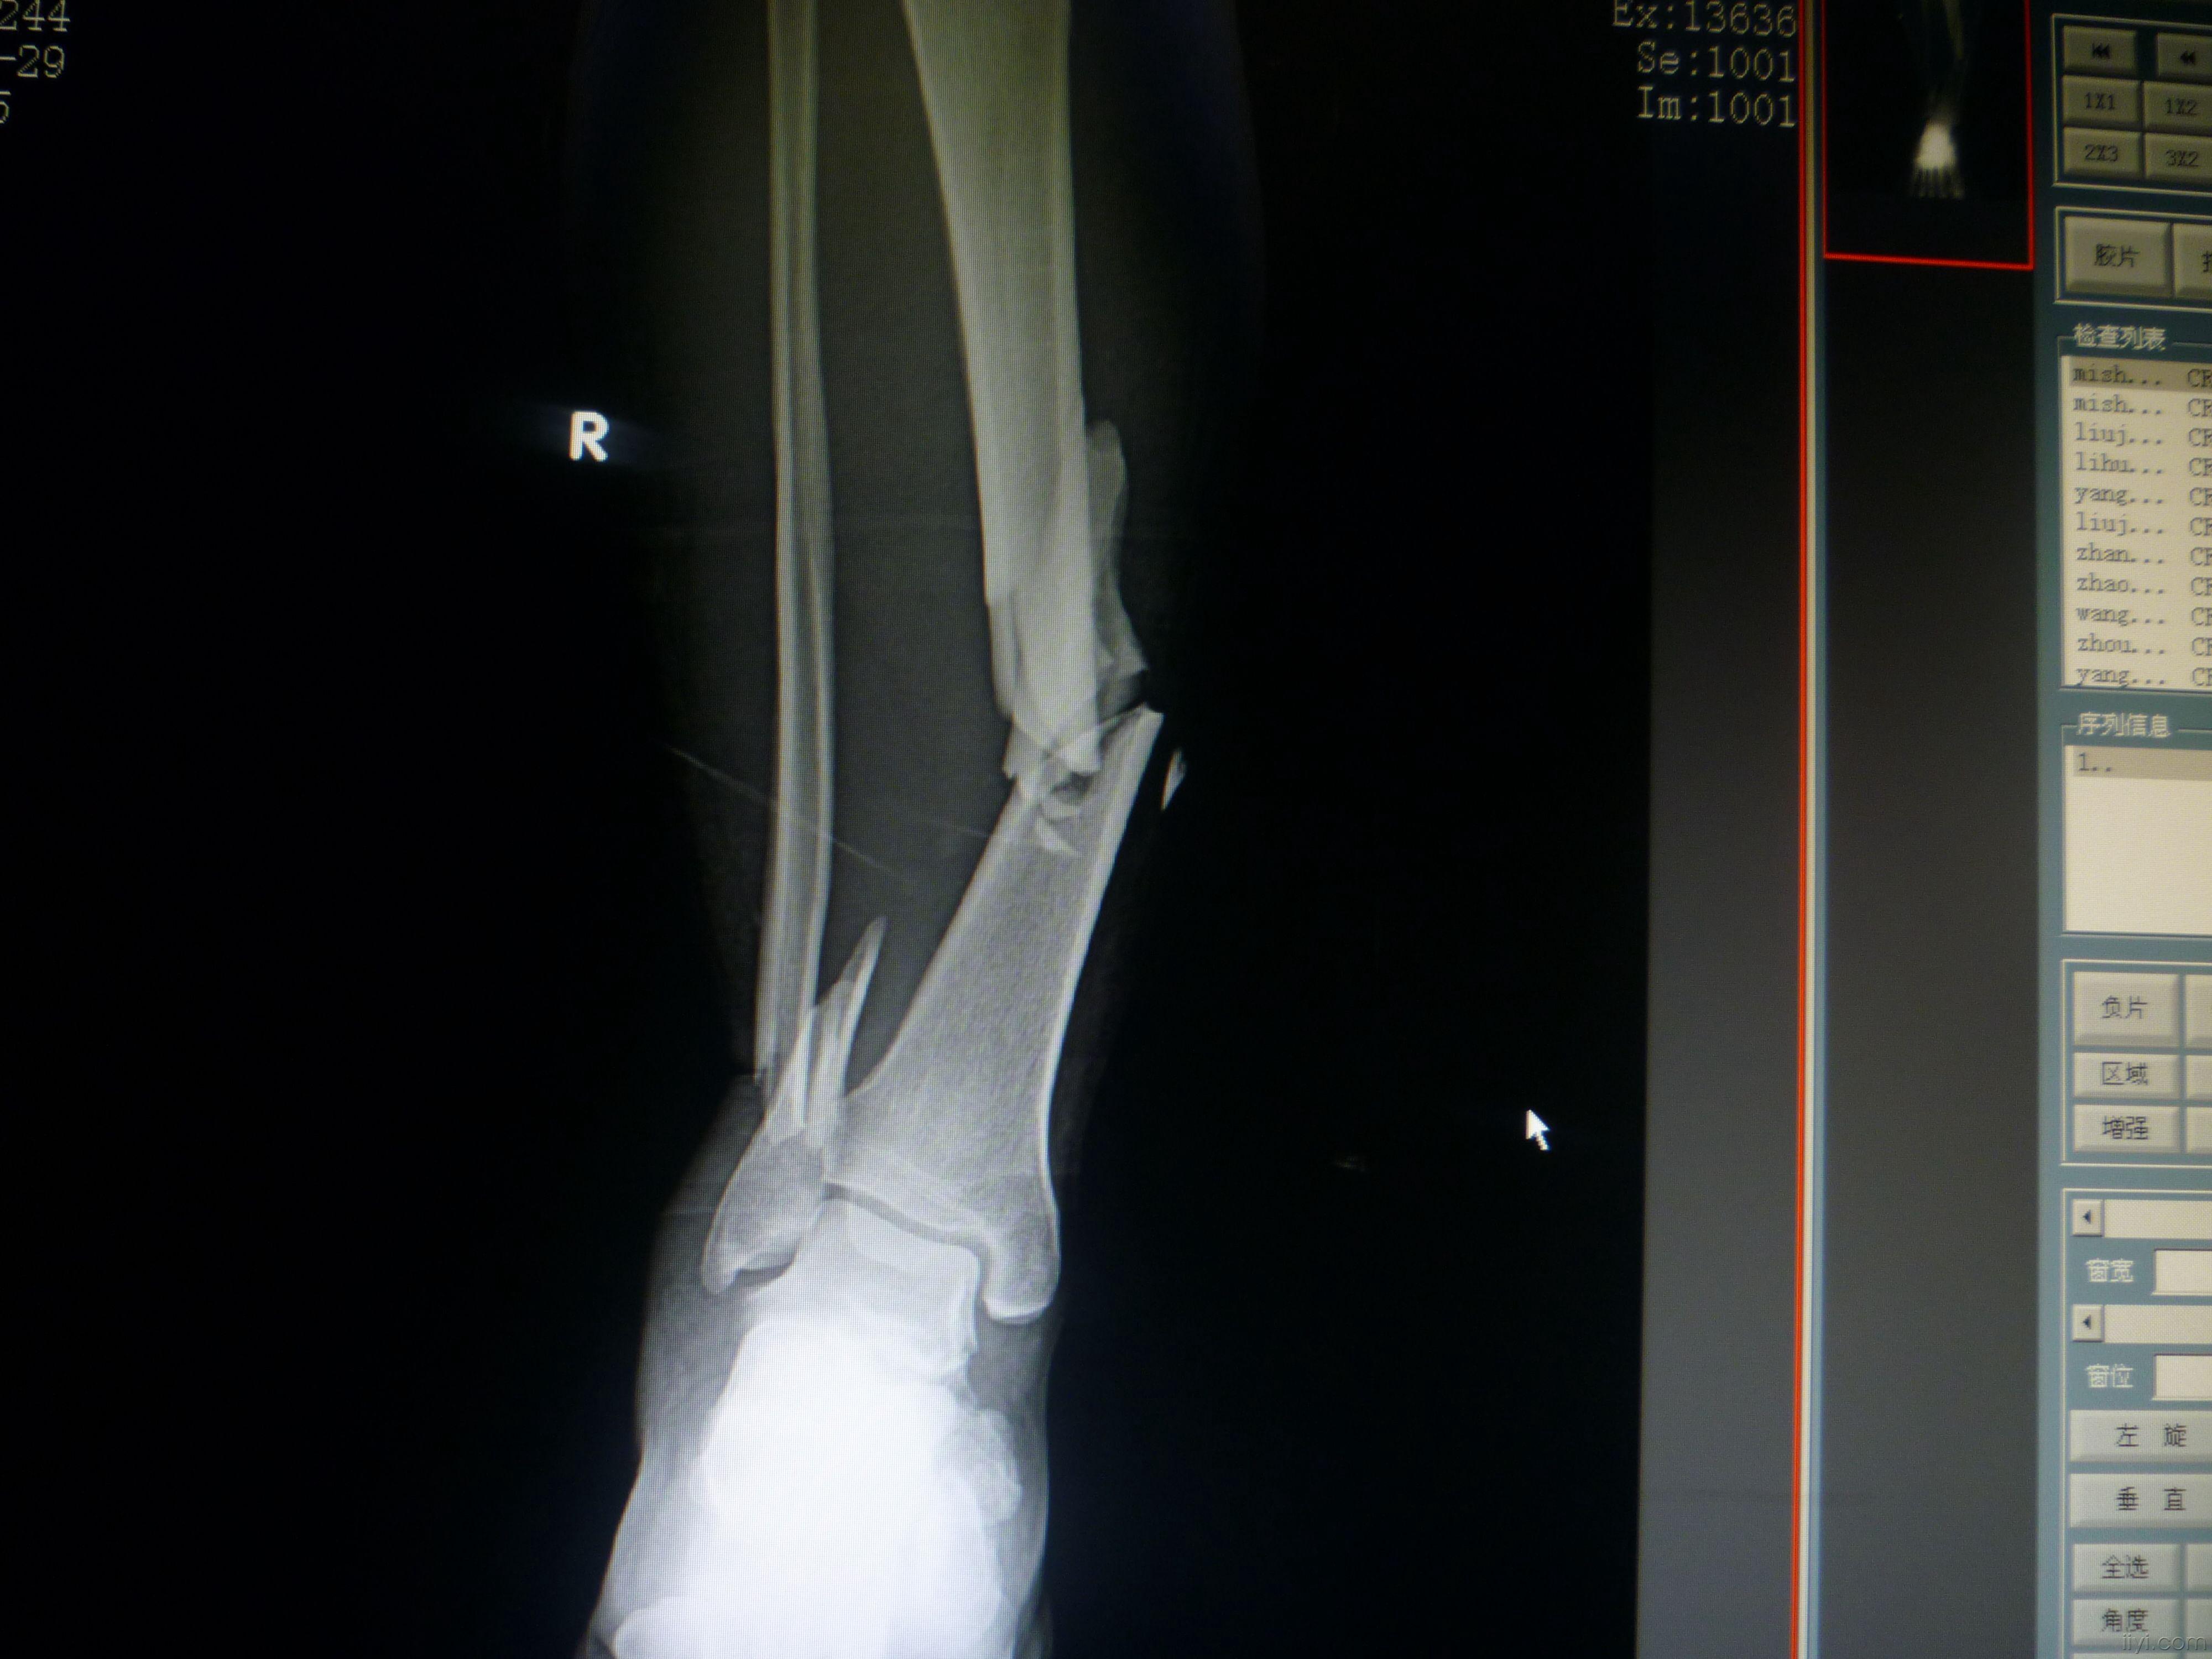

一例严重的胫腓骨远端粉碎骨折